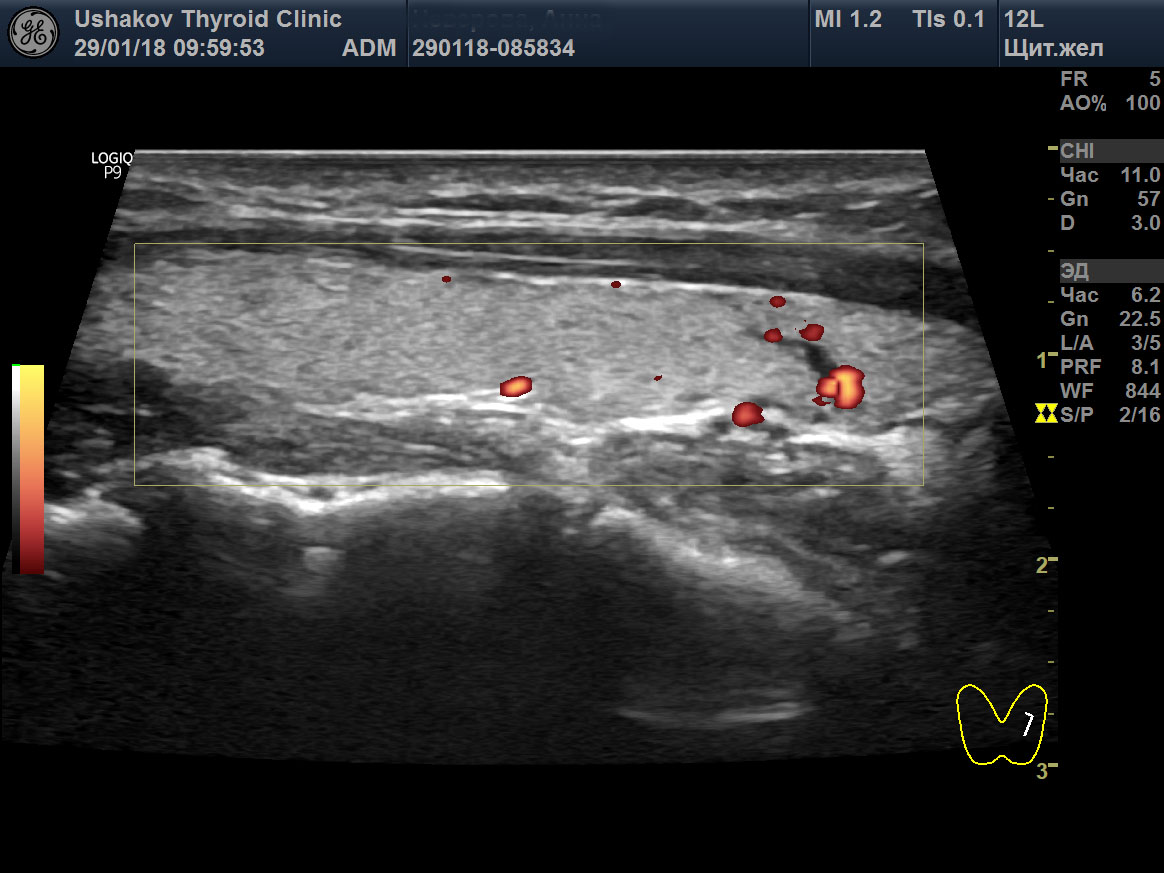

Гипертиреоз узи

Гипертиреоз узи 110 фото